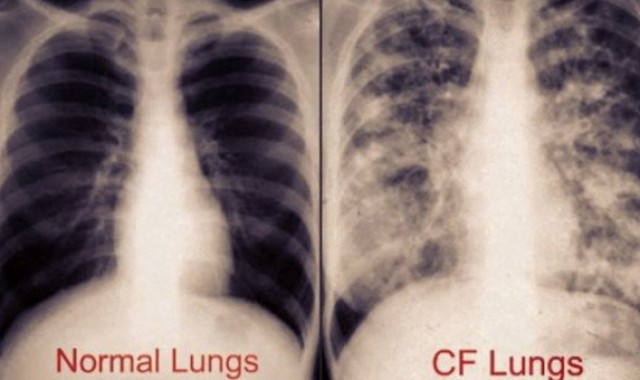

Όλες οι νέες εξελίξεις του 2015 από το 38ο Πανευρωπαϊκό & 29ο Αμερικάνικο Συνέδριο Κυστικής Ίνωσης στην καθιερωμένη Ημερίδα που θα πραγματοποιηθεί και φέτος από τον Πανελλήνιο Σύλλογο Κυστικής Ίνωσης “Ελληνική εταιρία για την Iνώδη Κυστική νόσο”. Νέες επαναστατικές θεραπείες, διατροφή, ψυχική υγεία, αναπνευστική φυσιοθεραπεία, ευρωπαϊκό registry καθώς και μεταμοσχεύσεις πνευμόνων σε Ελλάδα & εξωτερικό. Θα παρουσιαστούν τα πρώιμα και ενθουσιώδη αποτελέσματα των προγραμμάτων αναπνευστικής αποκατάστασης σε ενήλικες και άσκησης σε παιδιά με Κυστική Ίνωση που πραγματοποιούνται για πρώτη φορά στην χώρα μας. Τέλος θα τεθούν οι στόχοι και οι προκλήσεις που θα κληθούν να αντιμετωπίσουν οι ασθενείς με Κυστική Ίνωση τη νέα χρονιά που έρχεται σε αναμονή των καινοτόμων θεραπειών. Οι παρουσιάσεις θα γίνουν με την συμμετοχή του συνόλου των εξειδικευμένων ιατρών & επιστημόνων υγείας που παρακολουθούν ασθενείς με Κ.Ι. σε τμήματα και κέντρα από όλη την Ελλάδα: ‘’Σισμανόγλειο’’, ‘’Αγ.Σοφία’’, ‘’Αττικόν’’ , ‘’Ιπποκράτειο’’, ‘’Παπανικολάου’’, ’’Σωτηρία’’, ΤΕΦΑΑ ΑΠΘ, ΤΕΦΑΑ Ιατρική σχολή, Πανεπιστήμιο Αθηνών. Η Ημερίδα θα πραγματοποιηθεί το Σάββατο 14 Νοεμβρίου και ώρα 16.00 στο Αμφιθέατρο του Ιδρύματος Ιατροβιολογικών Ερευνών της Ακαδημίας Αθηνών (ΙΙΒΕΑΑ) υπό την Αιγίδα του ΕΟΜ, ‘’ανοίγοντας’’ ουσιαστικά τις δράσεις ευαισθητοποίησης και ενημέρωσης στα πλαίσια της Ευρωπαϊκής Εβδομάδας Κυστικής Ίνωσης 16-22 Νοεμβρίου.